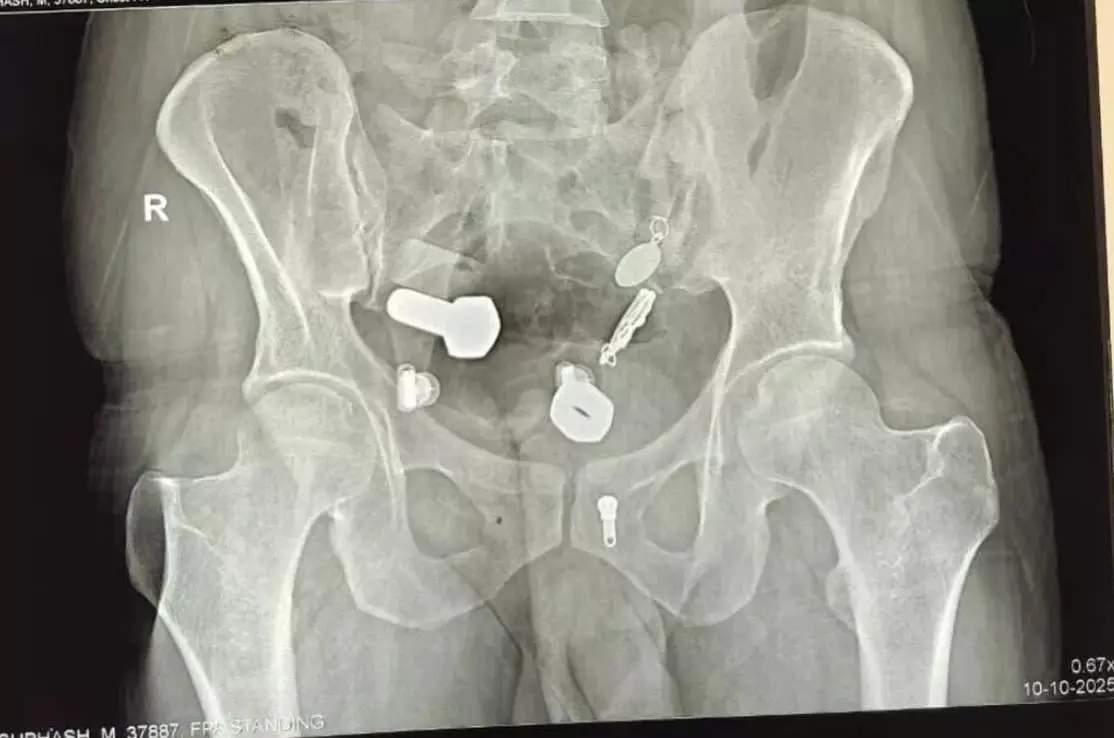

直到安排了影像學檢查,全體醫護人員才被螢幕上的畫面驚得說不出話:男子的食道中段卡著一整只手錶,而腸道裡更是像被刻意塞滿了「五金配件」,鐵片、螺絲、螺帽與大理石塊隨處可見,簡直是個移動的小型雜物堆。

印度齋浦爾一名34歲男子因劇烈腹痛嘔吐就醫,竟發現食道卡著整只手錶,腸道堆滿鐵片等硬物。醫護團隊歷3小時手術取出異物,研判其行為與精神疾病引發的幻覺及衝動有關,術後心理治療至關重要。(來源:網絡)

最終,團隊通過腹部小切口配合內視鏡夾取的方式,花費近3小時,才成功將所有異物逐一取出,術後男子的生命徵象逐漸穩定,順利進入留院觀察階段。